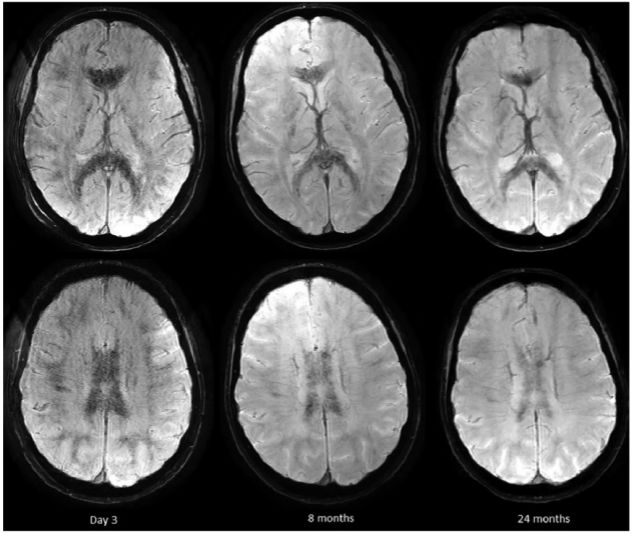

图2. 第5和第10天的1.5T及10年后的3T MRI图像。第10天FLAIR上胼胝体的信号增强,10年后消失;弥散受限程度第10天减弱,10年后消失;在第10年FLAIR上胼胝体膝部和压部的低信号由含铁血黄素沉积所致。